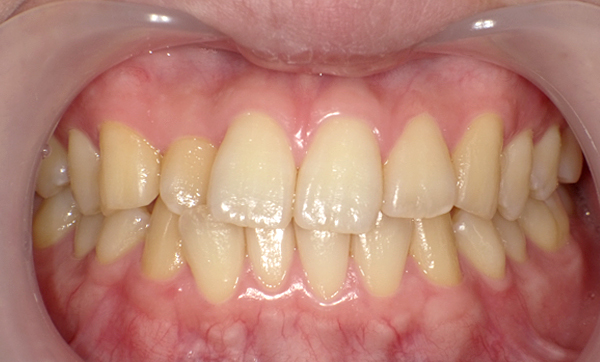

症例_009 「上下の前歯」症例

治療期間:7ヶ月金額:54万円+税20代女性捻転歯一部の反対咬合前歯のガタガタ